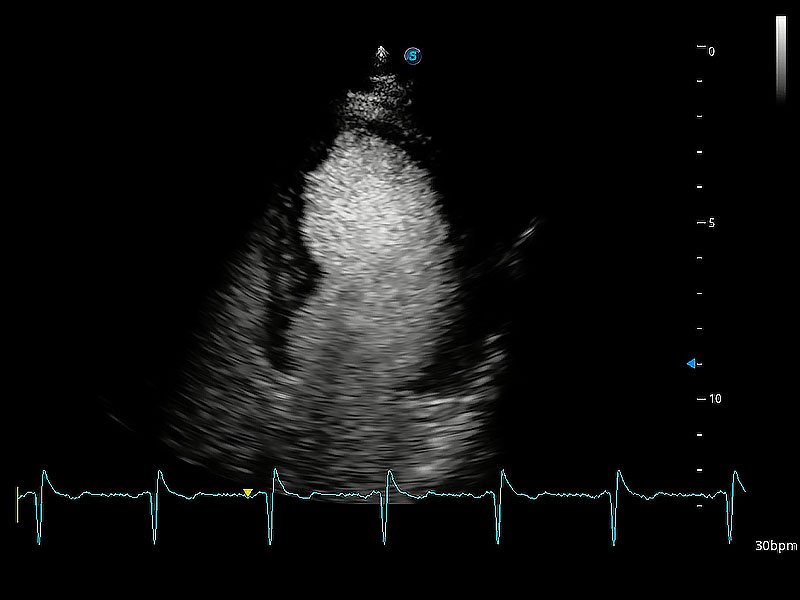

ProPet 80 配備了豐富的心臟探頭群、先進(jìn)的成像技術(shù)和專業(yè)的心臟測量工具,可幫助動物醫(yī)生為不同體型和生理結(jié)構(gòu)的動物提供心臟和心肌功能的全面評估。

實(shí)時用顏色表示心肌組織運(yùn)動,觀察和定量組織的運(yùn)動情況,對快速檢測與評估心肌的灌注和活性、電傳導(dǎo)及心肌收縮和舒張功能等均能提供重要的診斷信息。